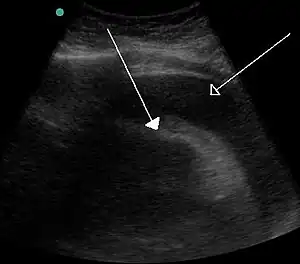

Bladder tamponade is obstruction of the urinary bladder outlet due to heavy blood clot formation within it.[3] It generally requires surgery.[3] Such heavy bleeding is usually due to bladder cancer.[4]

- 1 2 Page 352 in: Guenter Schmidt (2006). Differential diagnosis in ultrasound: a teaching atlas. Stuttgart: Thieme. ISBN 978-3-13-131891-6.